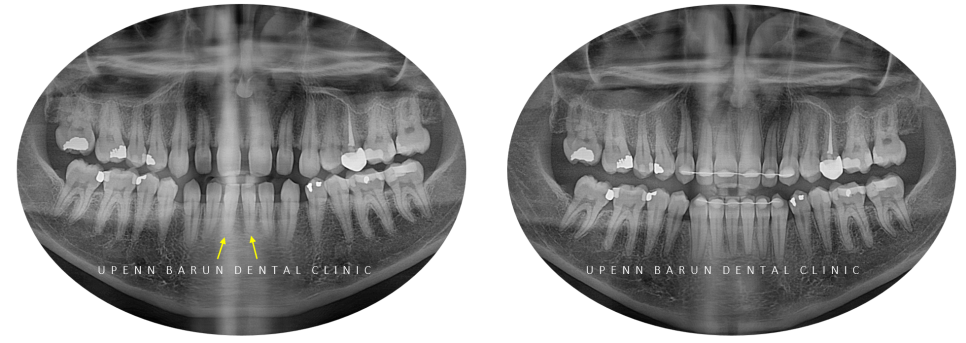

환자분께서는

치아사이의 공간이 벌어져 있을뿐만 아니라

앞니끼리 맞닿아

치아의 뿌리가 짧아져

치아의 수명에 좋지않은 영향을 주고 있는 상태였습니다 T^T

교정기간: 23/7~ 24/6